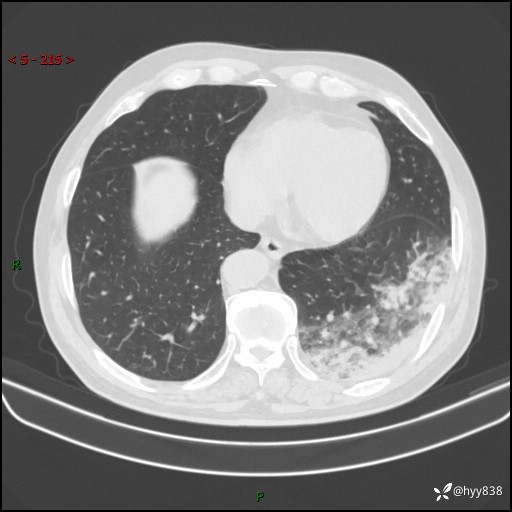

【患者信息】:59岁/男

【主诉】:发热伴咳嗽3天

【现病史及既往史】:患者3天前无明显诱因出现发热,体温最高达38.6℃,伴有咳嗽,干咳为主,感乏力、肌肉酸痛,无明显头晕头痛、鼻塞、流涕、呼吸困难、胸痛、恶心呕吐、腹痛腹泻、尿频尿急等不适,于当地诊所输液治疗3天感症状无好转,仍有间断发热、咳嗽,现为求进一步诊治,于我院门诊就诊,门诊以“发热待查”收入我科进一步诊治。 患者自发病以来,精神、饮食、睡眠欠佳,大小便正常,体力、体重无明显变化。

【检查】:胸部CT平扫